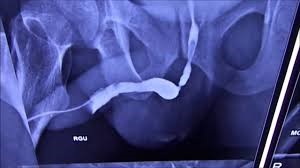

Patients suffering from urethral stricture may experience weak urine flow, frequent urination, and discomfort. Early diagnosis and timely treatment are essential to prevent complications such as bladder damage or recurrent infections. Dr Bhaskar employs the latest techniques, including VIU Laser (Visual Internal Urethrotomy) and urethroplasty, to restore normal urinary function effectively.

The treatment plan is customized based on the severity and location of the stricture. Minor strictures can often be treated with minimally invasive laser procedures, while more complex cases may require urethroplasty or reconstructive surgery. Dr Bhaskar combines his extensive experience with advanced technology to ensure maximum success and rapid recovery.